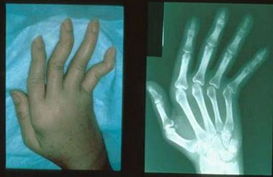

风湿性关节炎是溶血性链球菌所致上呼吸道感染后引起的一种反复发作的急性或慢性的全身结缔组织的炎症疾病,以心脏和关节受累最为明显。由于多数关节炎是风湿热的早期症状之一,其关节受影响的成人占91.7%,儿童占55.7%。由于风湿性关节炎发病较急,病初全身以发热和显著的关节红、肿、热、痛为主要表现,如不积极治疗,则会形成慢性风湿性关节炎,一些患者甚至会丧失劳动能力和生活自理能力,约50%的患者可发展成心脏病而危及生命。

风湿性关节炎分急性或慢性两种类型,慢性风湿性关节炎患者多见于中老年人群。风湿性关节炎虽有长期关节疼痛,但无关节活动功能障碍。起病时多有周身疲乏、食欲减退、出汗、烦躁等症状。大多数患者均可出现发热,呈不规律低热或中度发热,也有呈驰张热或持续高热者。局部症状主要表现为关节红、肿、热、痛等。病变主要侵犯膝、踝、肩、肘、腕等大关节,但少数也侵犯四肢小关节及颞颌关节和脊柱关节。特别是关节疼痛,呈游走性,也可以数个关节同时受累。关节外症状包括心脏病变及皮肤改变。>>>您目前的症状是什么?有没有引发其它并发症?点击免费咨询专家